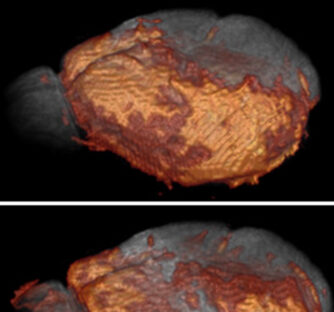

IRM au Mn2+ pour le suivi de l'activité de la Connexin 43